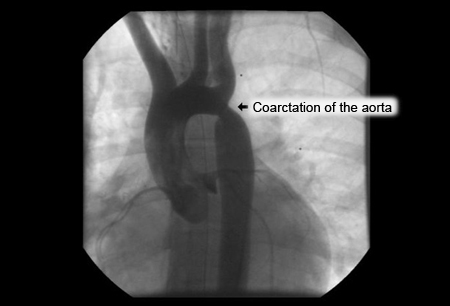

Angiography in the ascending aorta shows a focal area of narrowing after the left subclavian artery

From the personal collection of Jeffrey Gossett, MD, Children's Memorial Hospital, Northwestern University, Chicago; used with permission